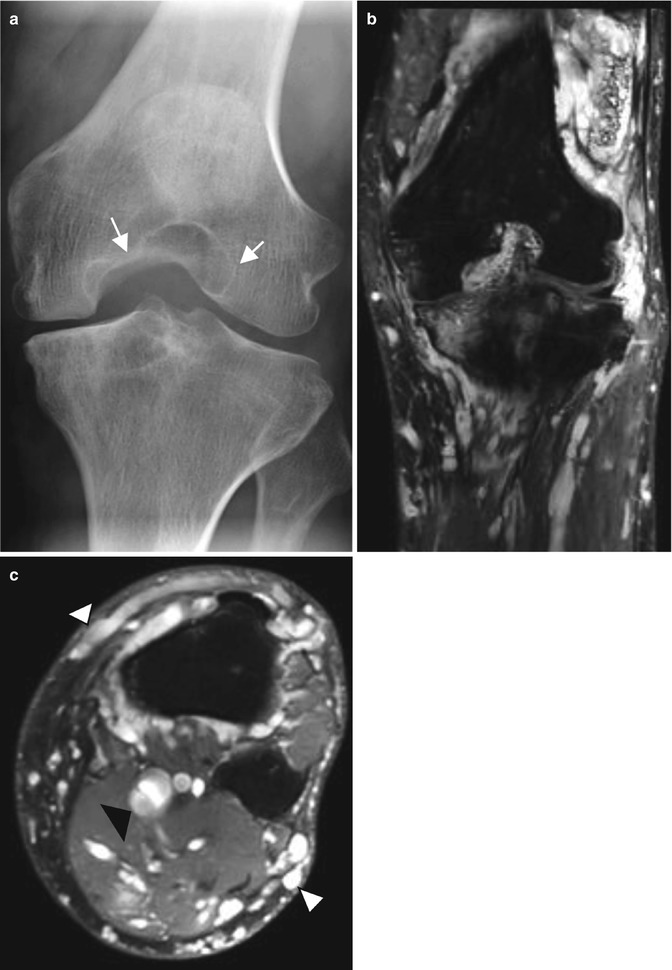

Patient with diffuse and infiltrative venous malformation of the knee. (a) Plain radiograph. (b) Coronal T2-weighted image with fat saturation. (c) Axial T2-weighted image with fat saturation. (a) Plain radiograph shows a widening of intercondylar notch with erosion of the medial femoral condyle. (b, c) MRI shows infiltrative and serpentine vascular spaces with involvement of multiple compartments of the knee. Hyperintense nodular and serpentine areas of vascular vessels are seen in the subcutis (arrowheads), muscles and joint. Note the dilated deep veins (black arrowhead)